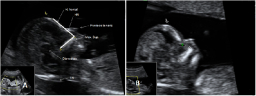

Ecografía semana 12 ángulo frontomaxilar

Con la ecografía de la semana 12 de embarazo se pueden detectar algunos signos (marcadores) característicos de los fetos con alguna anomalía cromosómica. Uno de ellos es el ángulo que forman el maxilar superior y el hueso frontal. Qué mide el ángulo frontomaxilar del bebé Se mide el ángulo...

Ecografía de la translucencia nucal

La ecografía de la derecha muestra a un bebé con un cribado positivo que resultó tener un síndrome de Down. La translucencia nucal (o pliegue nucal) por ecografía se ve como un espacio negro en la parte posterior del cuello, acotado por las marcas del ecografista. El bebé de la izquierda...

Ecografía para medir al feto

En la ecografía 2D de este feto de 12 semanas, podemos apreciar la medida cráneo-caudal o CRC (desde la cabeza hasta la rabadilla o coxis), que en este caso es de 6,2 centímetros. Estirado, el bebé mide más -algo más de 10 centímetros-, pero los especialistas suelen tomar esta medida, más...